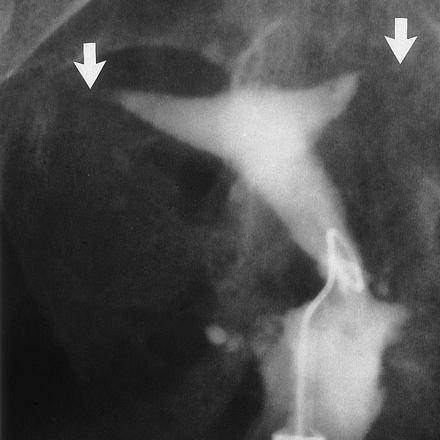

Her iki tüpün de kapalı olduğundan emin olmak için laparoskopi (karın içerisine kamera ile bakılması ameliyatı) yapılması gerekir. Rahim filmi (HSG) bu konuda yanıltıcı olabilir çünkü rahim filminde kapalı görülen tüplerin bir kısmının aslında açık olduğu laparoskopide görülmektedir. Rahim filmi çekimi sırasında tüpler spazm (kasılma) nedeniyle kapalıymış gibi izlenebilir.